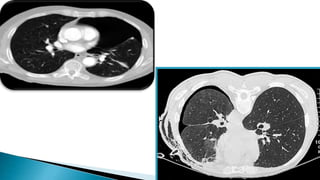

CT scanning is done if accurate size

estimates are required.

It is only recommended to difficult cases such

as patients in whom the lungs are obscured

by overlying surgical emphysema.

To differentiate a pneumothorax from

suspected bulla in complex cystic lung

disease.